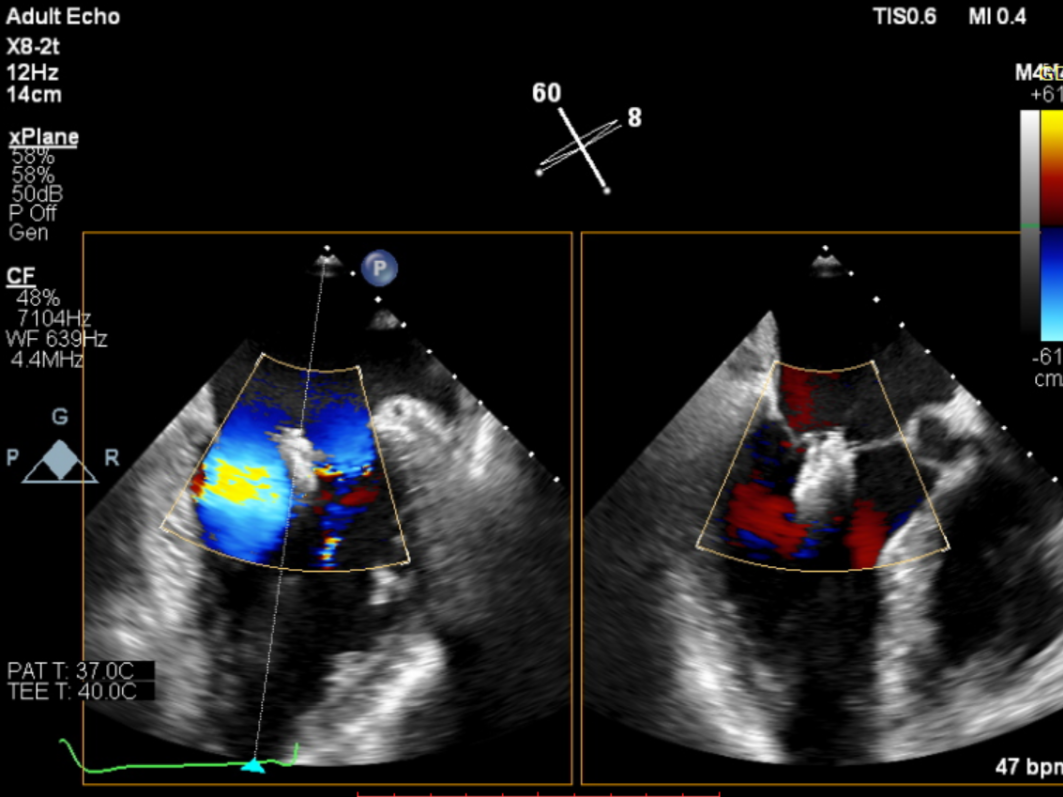

术前,罗建方、范瑞新教授团队进行了多次缜密术前讨论,最后决定为患者采用DragonFly™二尖瓣瓣膜夹。经充分的术前讨论后,心内科罗建方、范瑞新教授团队,在超声指导下,麻醉和体外循环团队保驾护航,瓣膜夹平稳释放,成功植入一枚DragonFly™瓣膜夹,随即进行DSA及心脏超声复查,观察到植入的瓣膜夹位置精确,患者二尖瓣反流从4+减少到1+以下,手术取得了圆满成功。